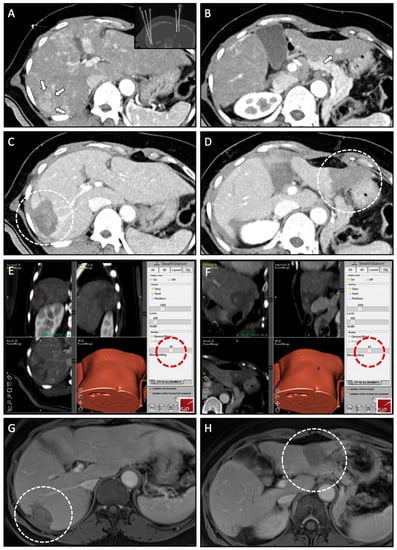

As part of the SRFA procedure, an intraprocedural image fusion of pre- and post-ablation contrast-enhanced CT scans (planning/control CT scan as part of the procedure) is performed using a rigid registration tool implemented in the navigation software with final manual adjustment by using anatomical structures. It is an integral and mandatory component of the SRFA workflow (Figure 3) for intraprocedural evaluation of the technical success. In case of incomplete ablation (residual tumor; lack of sufficient safety margin), the intervention may be continued in the same session.

Figure 3.

Case of a 57-year-old male with simultaneous treatment of two HCCs (right and left liver lobe) using SRFA. (A,B) Planning CT scan in arterial phase of the SRFA procedure with a 30-mm HCC nodule in liver segment VI (white arrows) and a 9-mm HCC nodule in liver segment III (white arrow); Maximum Intensity Projection (MIP) of the non-enhanced control CT scan showing the position of seven coaxial needles in the upper right corner of (A). (C,D) Control CT scan after ablation with corresponding necrosis zones in liver segment VI and III (white dashed circles). (E,F) Three-dimensional views of the intraprocedural image fusion of the contrast-enhanced planning and final control CT scan using the rigid-registration tool from the navigation system with the possibility to switch between images using the blending function (red dashed circle); verification of complete necrosis including a sufficient safety margin. (G,H) Follow-up MRI scan 18 months after SRFA, showing no evidence of LTP with shrinking necrosis zones (white dashed circle).